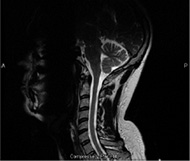

MRIの診断画像(イメージ)